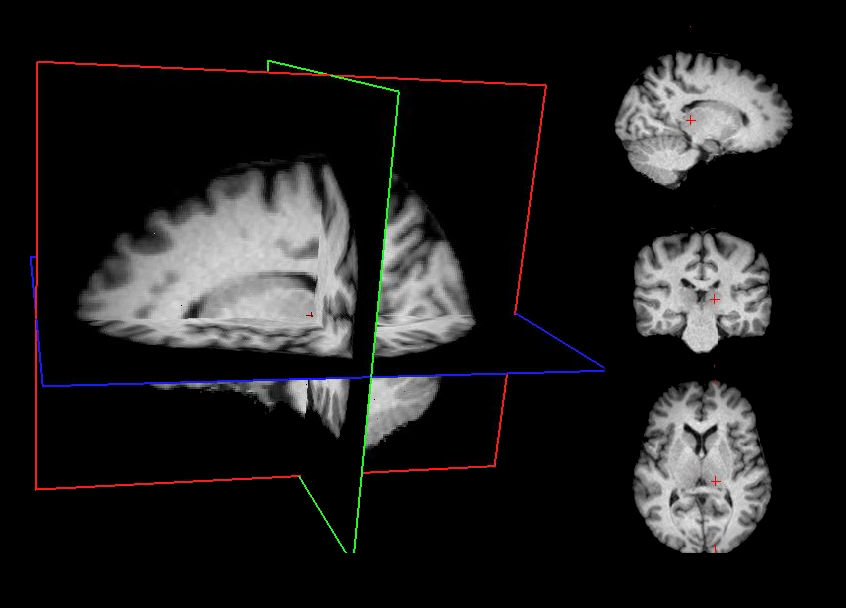

Minimally preprocessed data are generated using a standardized sequence of lightweight processing steps applied to the raw T1-weighted (T1w) MRI images. This workflow combines skull stripping, bias field correction, and spatial normalization using widely adopted neuroimaging tools. This minimal preprocessing pipeline ensures that the data are standardized and ready for subsequent processing stages while maintaining maximal fidelity to the original raw images.

Affine registration to MNI space Spatial alignment is carried out using FSL FLIRT [3] with a 9‑degree‑of‑freedom (DOF) affine transformation (translations, rotations, and scaling; no shearing). This step registers the T1w image to the MNI template while preserving overall anatomy.